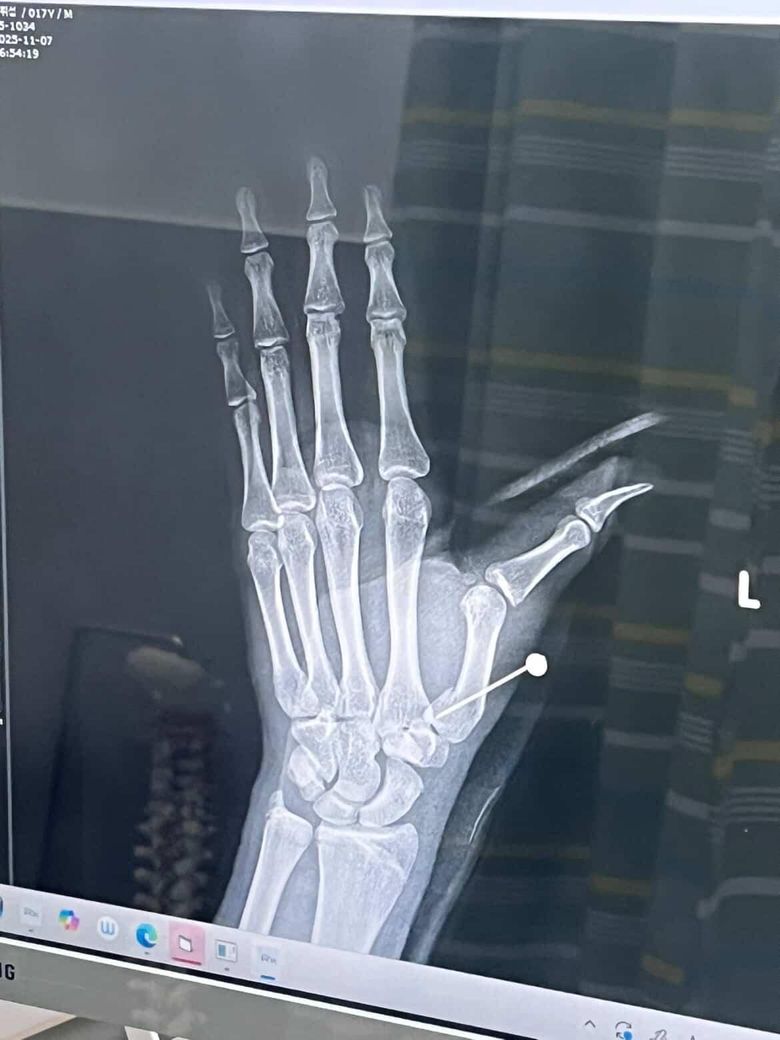

핀수술후 단차?재수술여부.휴유증

수술전 간단한수술이라고 걱정말라고하시더니 끝나고나서90%잘됐다.100%까지할려면 피부절개해서 해야하는데 이정도면 잘됐다고 하셔서 안심하고 있었는데 3일뒤 사진을보니 단차도 그대로인것같고 주변에서 재수술 권하고있는데 꼭해야하나요?향후 후유증이생길까요?고등학생이라 오래 입원할수있는상황도아니고 전신마취안하면 두번다시 안한다고 하고있습니다.

• 2번 째 사진